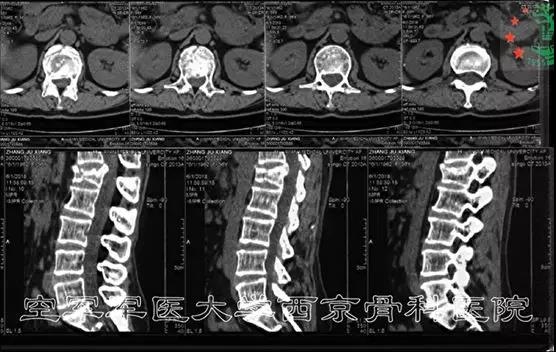

术前CT

术前MRI